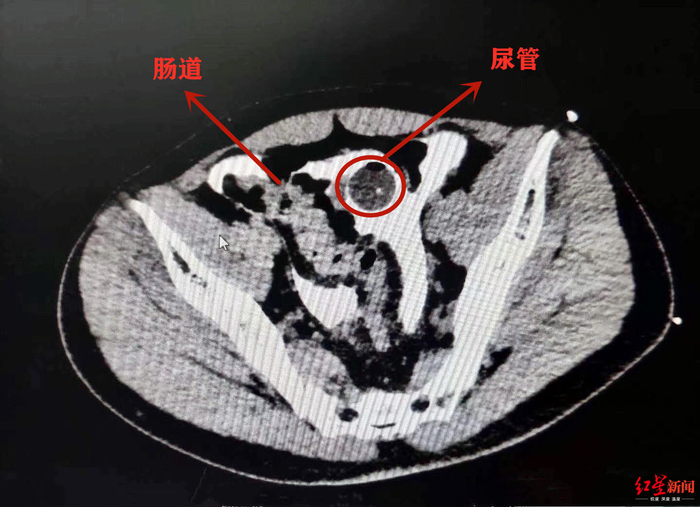

辗转几家医院,小李在星期天晚上被送到了成都市第三人民医院。该院泌尿外科副主任医师袁仁斌博士说,小李膀胱有一个4*3cm的破洞,尿管也顺着洞“跑”到了腹腔内。因为尿液在腹腔内蓄积了很长时间,已经引发了比较严重的腹膜感染,“如果再不及时手术,可能生命都会受到威胁。”

当晚,小李便接受了修补手术。好在,经普外科医生接力探查,发现他腹腔内的其他脏器未受到伤害。经进一步康复,小李即可出院。